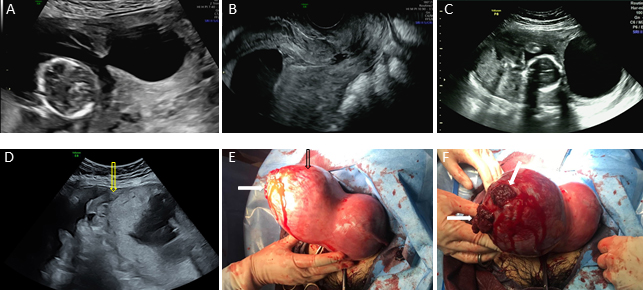

Fig. 6.The two-dimensional gray-scale ultrasound images and

intraoperative photos of a case of type III angular pregnancy. Ultrasound

examination at 15 weeks of gestation: (A) The fetus was found in the right

angular, and there was an adhesive band between the right angular and the uterine

cavity. (B) Only amniotic fluid without fetal structure was found in the middle

and lower part of the uterine cavity. Ultrasound examination at 20 weeks of

gestation: (C) The fetus was curled up in the right angular, and there was an

adhesive band between the right angular and the uterine cavity. (D) Rupture of

the right angular and hemoperitoneum (yellow arrow indicates the rupture of right

angular). Intraoperative photos: (E) The black arrow indicates that the right

angular is obviously protruding, and the white arrow indicates the rupture of the

right angular. (F) The white arrow indicates that two lacerations of 50.0 mm

One case was previously diagnosed as normal early intrauterine pregnancy in a

separate hospital; however, the right angular protuberance without an angular

pregnancy was identified during an ultrasound examination at the 15th week of

pregnancy by a junior doctor at our institution. Five weeks later, the patient

experienced pain in the right lower abdomen, with a clear ultrasound diagnosis by

a senior doctor of a right angular and interstitial pregnancy with rupture of

angular location. The patient developed hemorrhagic shock and accepted emergency

laparotomy, with two lacerations (50.0 mm